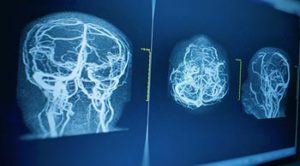

Vascular Imaging